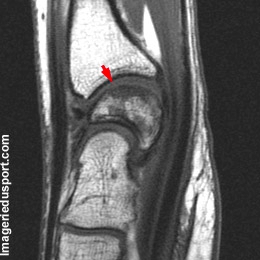

C - IRM, coupe sagittale T1 : bascule relative dorsale du semi-lunaire par rapport au radius et au capitate. Cependant, cet aspect est à confronter à des clichés standards. Hyposignal sous chondral du lunatum.

Maladie de Kienböck (stade II de Golimbu).